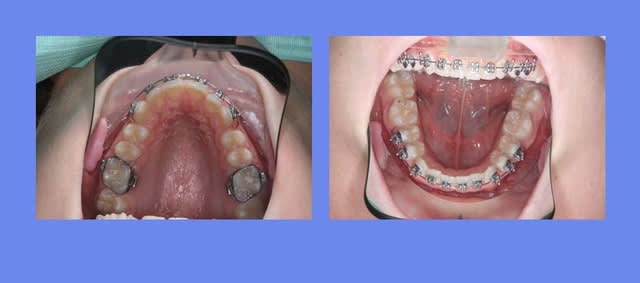

suite,

J’ai traité ce cas avec un Q.H. en Sup., puis avec un MB. Inf., puis seulement un segmenté Sup. car le bas est Tjs. pl

us lent à réagir que le haut

on voit que l’arcade du bas est mieux reformée que l’arcade du haut

le prochain Rdv. est pour coller la fin du haut

@+ Bjc.